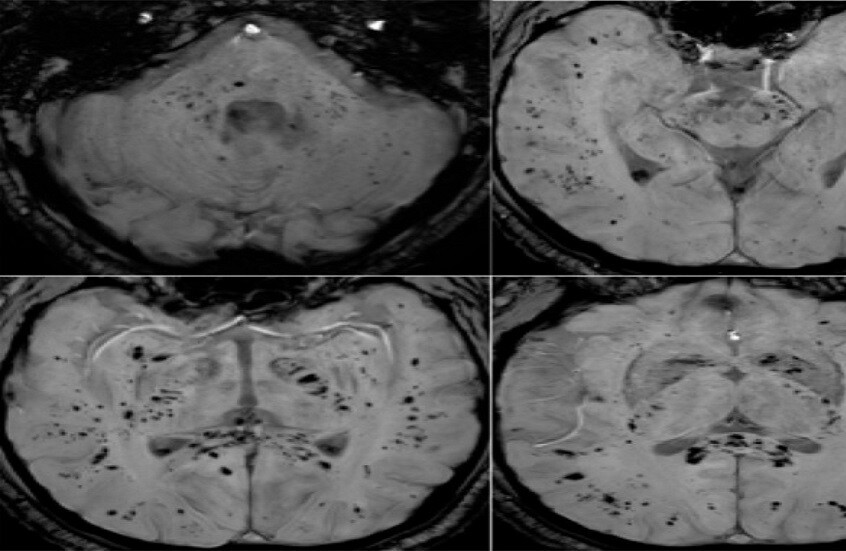

تحليل بالرنين المغناطيسي يكشف تأثير كوفيد-19 المستمر على الدماغ

أظهر تحليل صور بالرنين المغناطيسي أن فيروس كوفيد-19 يترك أثرا لا يُمحى في الدماغ، ويستمر تأثيره حتى بعد التعافي التام.

أظهرت دراسة حديثة أجراها علماء في جامعة غريفيث الأسترالية ونُشرت في مجلة Brain, Behavior, & Immunity Health أن فيروس كوفيد-19 لا يؤثر على الجهاز التنفسي فحسب، بل يترك أثرا ملموسا على الدماغ، ويستمر تأثيره حتى لدى الأشخاص الذين يعتبرون أنفسهم متعافين تماما، حتى إذا لم تظهر عليهم أعراض واضحة.

وأوضح الباحث الرئيسي الدكتور كيران تاباليا أن الفريق استخدم طرق التصوير بالرنين المغناطيسي متعددة الوسائط لدراسة المادة الرمادية والبيضاء في الدماغ، وهي مهمة للذاكرة والوظائف الإدراكية والصحة العامة للدماغ. ووجد الباحثون اختلافات ملحوظة في أنسجة الدماغ وموادها الكيميائية العصبية وشدة الإشارة وبنية الأنسجة لدى المتعافين من كوفيد-19، حتى في حالات الإصابة التي اعتبرت بسيطة.

وأضاف تاباليا: "تبين أن التغيرات في أنسجة الدماغ مرتبطة بشدة الأعراض"، ما قد يفسر مشكلات إدراكية طويلة الأمد مثل تدهور الذاكرة والتركيز، والتي قد تستمر لشهور أو حتى سنوات بعد الإصابة.

وتشير النتائج إلى العواقب العصبية طويلة المدى للفيروس، وهو ما أكدته أيضا منظمة الصحة العالمية، التي أعلنت مؤخرا أن الأعراض طويلة الأمد بعد كوفيد-19 لا تزال مشكلة خطيرة تؤثر على عدد كبير من الناس.